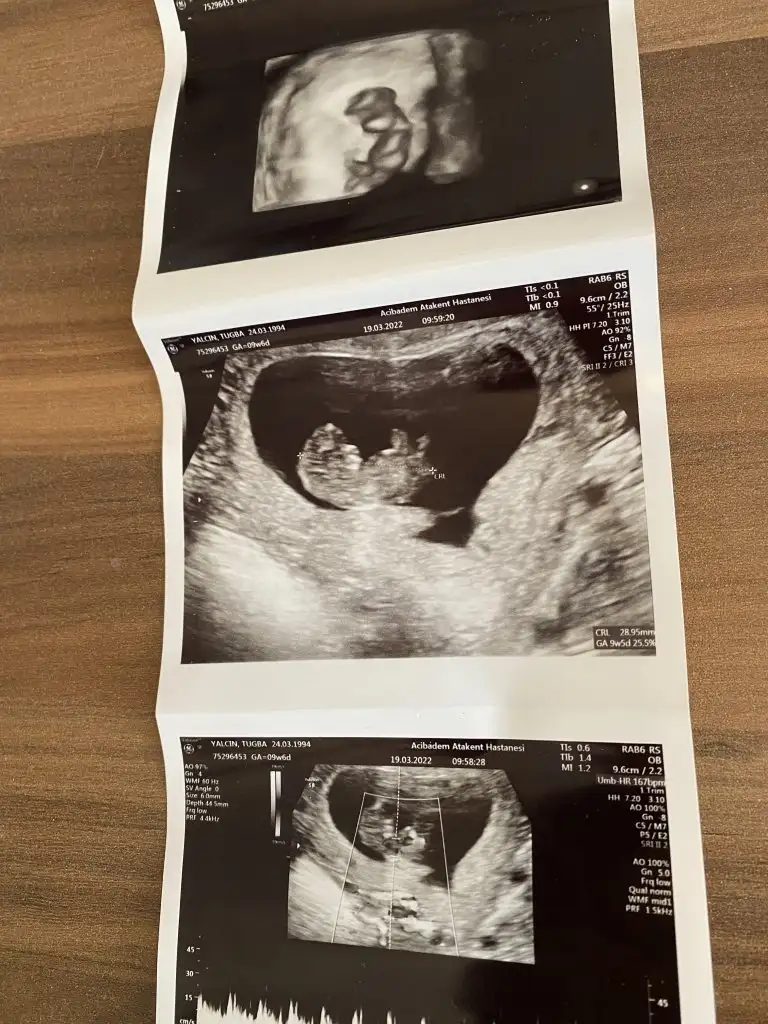

9+5 zamanından ultrason görüntüsü. Karından bakıldı, bana da bakar mısınız rica etsem çok merak ediyorum :)Selam Kızlarbir çok kişi gruplardan beni bilir. Yine yetiştim imdatlara

Çoook uzun bir süre araştırma okuma yaptıktan sonra sizlere bu başlığı açtım çevremde tüm gebelere de denedim. Bunun sırrını çözen İnstagramda (isim vermeyim) işi ticarete dökmüş bile.Nub, Ramzi,Çin Rus Japon Takvimleri, Yüzük Yöntemi bir çok şey size sayabilirim.

5 ve 14. haftaya kadar olan ultrason fotolarınızı paylaşın. Vajinadan mı yoksa karından mı çekildiğini ve kaç haftalık olduğunu da mutlaka belirtin.

Not: Tahmin yaptığım anneler cinsiyet öğrendikten sonra lütfen bana geri dönüş yapın